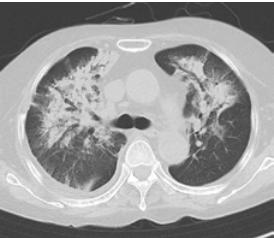

入院后继续使用外用皮质类固醇,并在住院第6天开始口服依替酸酯,剂量为20mg/天。入院第7天,患者出现缺氧,胸部x线及CT证实双侧浸润影以右肺野为主(图3)。

图3、患者肺CT,患者入院第七天出现双侧浸润影

由于抗生素治疗无效,进行了支气管镜检查。细支气管肺活检显示有组织的图像,中性粒细胞、巨噬细胞、淋巴细胞浸润,纤维蛋白渗出肺泡间隙(图4a, b)。

图4、病理

细支气管肺活检显示有组织的图像,中性粒细胞、巨噬细胞、淋巴细胞浸润,纤维蛋白渗出肺泡腔。(a: HE,×20, b: HE,×400)